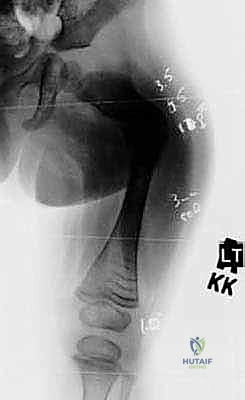

الخطوة الأولى: التخطيط الجراحي الدقيق (Pre-operative Planning)

قبل العملية، يقوم الدكتور هطيف بإجراء دراسة شاملة لصور الأشعة السينية (X-rays) المأخوذة بدقة، لحساب زوايا التقوس بدقة متناهية، وتحديد نقاط بضع العظم (أماكن القص)، واختيار الحجم والطول المناسبين للمسمار التلسكوبي.

- يتم إجراء أشعة سينية للتأكد من بدء تكوّن الدشبذ العظمي (Callus) حول مناطق القص.